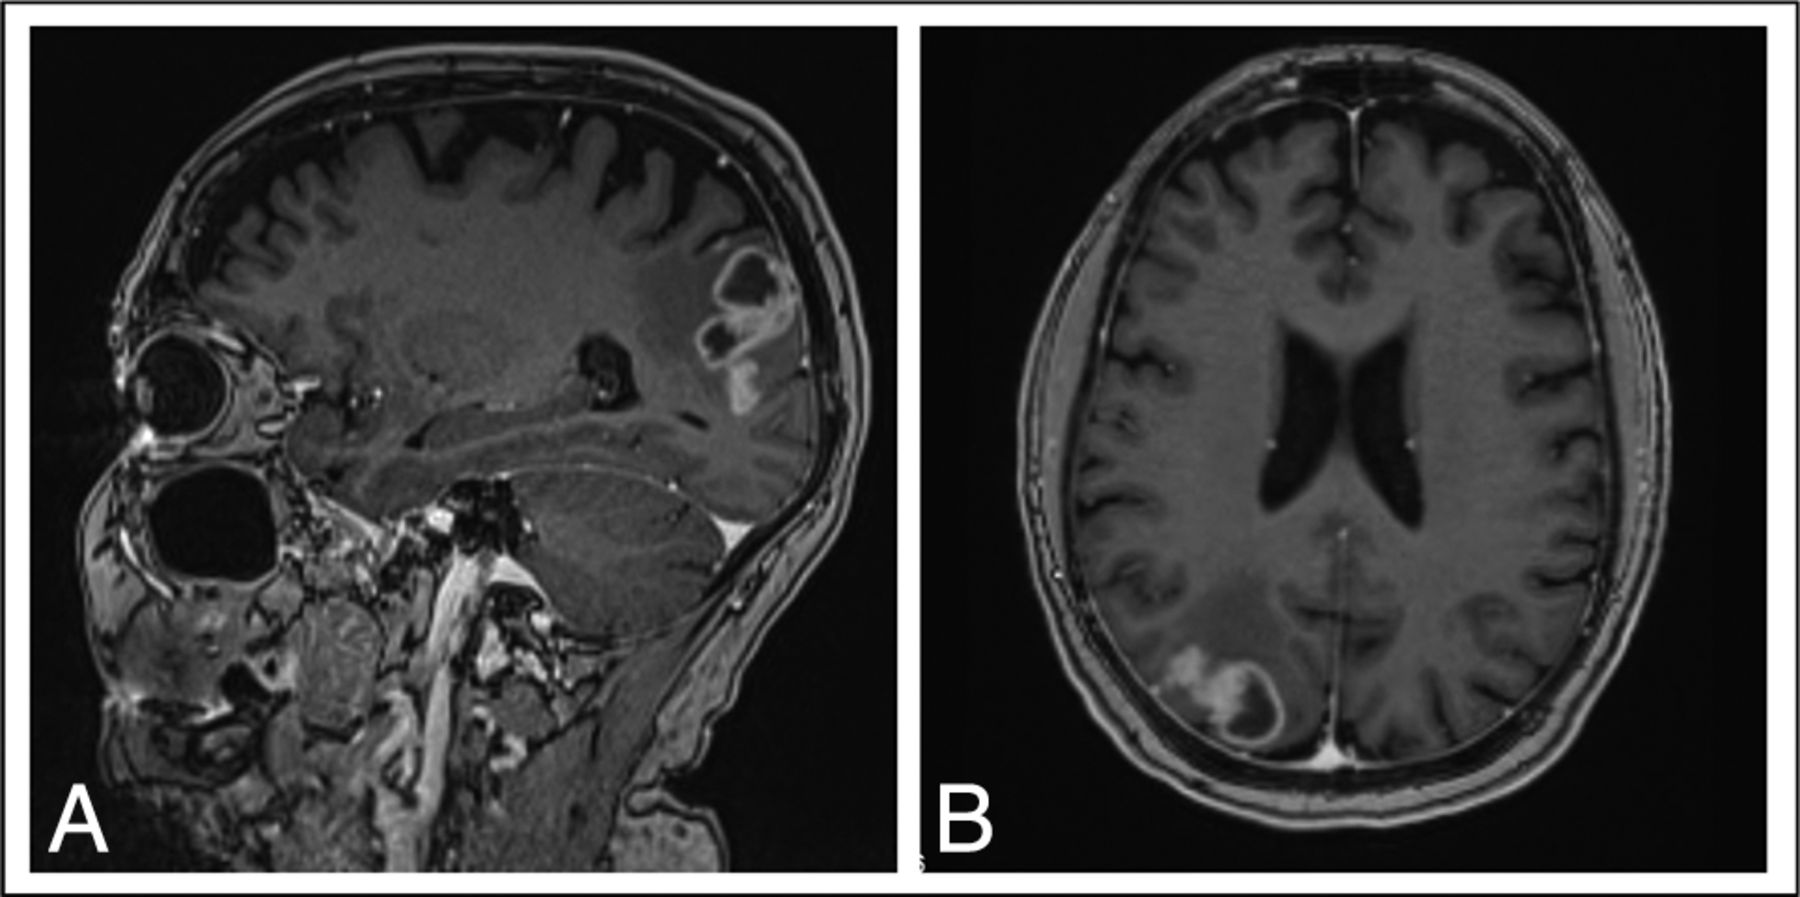

A 62-year-old man with early-stage EGFRm NSCLC (exon 19 deletion) was initially treated with a left lower lobectomy. Thirty-four months later, he developed pulmonary metastases and began treatment with gefitinib. Twelve months after that, he developed headaches, and a brain MR imaging revealed a lesion with an appearance consistent with FLIP in the right cerebellum (Fig 3) and several additional small lesions in the brain parenchyma. He was treated with WBRT and continued gefitinib. An MR imaging 3 months later revealed a complete response in his other brain lesions and a partial response in the FLIP. Unfortunately, MR imaging 4 months later showed isolated progression of the FLIP, with extension along the cerebellar folia and minimal infiltration into the brain parenchyma. He remained asymptomatic. The FLIP lesion was targeted with focal radiation therapy, and 3 months later, MR imaging showed stable disease. Unfortunately, MR imaging performed 4 months later demonstrated radiologic progression of the FLIP, which continued for 12 months until he died due to neurologic causes. Throughout this, no additional brain lesions were noted, and his extracranial disease remained stable.

Brain MR imaging for patient 2, a 62-year-old man with EGFRm NSCLC. Sagital (A) and axial (B) projections demonstrate an enhancing lesion spreading along the cerebellar folia after several months of treatment with gefitinib.